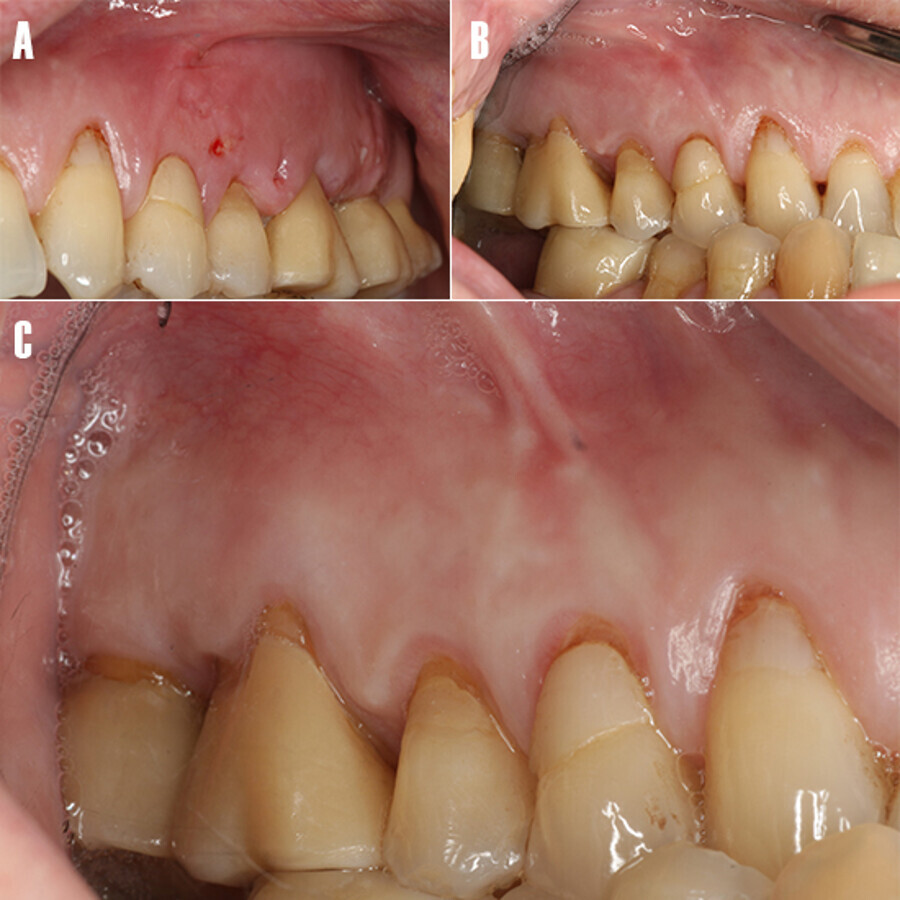

A la exploración clínica se observan recesiones gingivales generalizadas, y restauraciones con resina en la zona cervical de los dientes (Fig. 1A), presenta una restauración ceramo-metálica a nivel de 2.6 y 2.7, los tejidos blandos anexos al diente afecto se observan tumefactos, sin secreciones purulentas ni tracto sinuoso (Fig. 1B).

Figura 1. Fotografía intraoral. A) Vista frontal: nótese las recesiones gingivales generalizadas y restauraciones con resina en cervical de los dientes. B) Imagen lateral: nótese la zona tumefacta a nivel de 26 y 27. C) Vista oclusal: se observa el absceso periodontal tumefacto extendiéndose de distal 25 a media 27.

El molar 2.6 presentaba dolor a la percusión. Tras la evaluación periodontal se observan bolsas periodontales y sangrado al sondaje en la zona mesio-vestibular de 2.7 y 2.8. Los valores medios de pérdida de inserción clínica (2mm), la profundidad de sondaje (1.7 mm), índice de placa (19%) y sangrado al sondaje (9%), nos indican que estamos ante un caso de periodontitis (Estadío I) de complejidad localizada (<30% dientes). El caso periodontal está modificado por la presencia de absceso periodontal/lesión endo-periodontal, recesiones gingivales, fuerzas oclusales traumáticas.